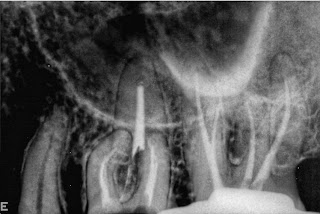

Caso Clínico do Prof. Jorge Vera: Pré-molar Inferior com Anatomia Interna Complexa - Lower premolar with complex anatomy

A lower premolar with complex anatomy, The second premolar will be extracted. The root canal was done after removing the Crown wich was then temporarily re-cemented. I use the M4 to loosen small K files for glide path and then the Twisted files were used for shaping.